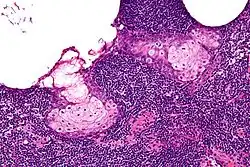

High magnification micrograph of a sebaceous lymphadenoma. H&E stain. | |

Sebaceous lymphadenoma is a benign tumour of the salivary gland.[1]

Sebaceous lymphadenoma is a tissue diagnosis, e.g. salivary gland biopsy.

It may be confused with a number of benign and malignant neoplasms, including Warthin tumour, mucoepidermoid carcinoma and sebaceous lymphadenocarcinoma.[2]